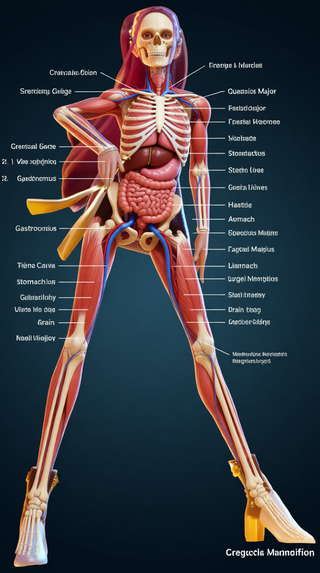

Creates ultra-detailed, multi-layer 3D anatomical visualizations from reference photos.Open

Creates ultra-detailed, multi-layer 3D anatomical visualizations from reference photos.Open

Transform photos into scientific anatomical illustrations.Open

Transform photos into scientific anatomical illustrations.Open